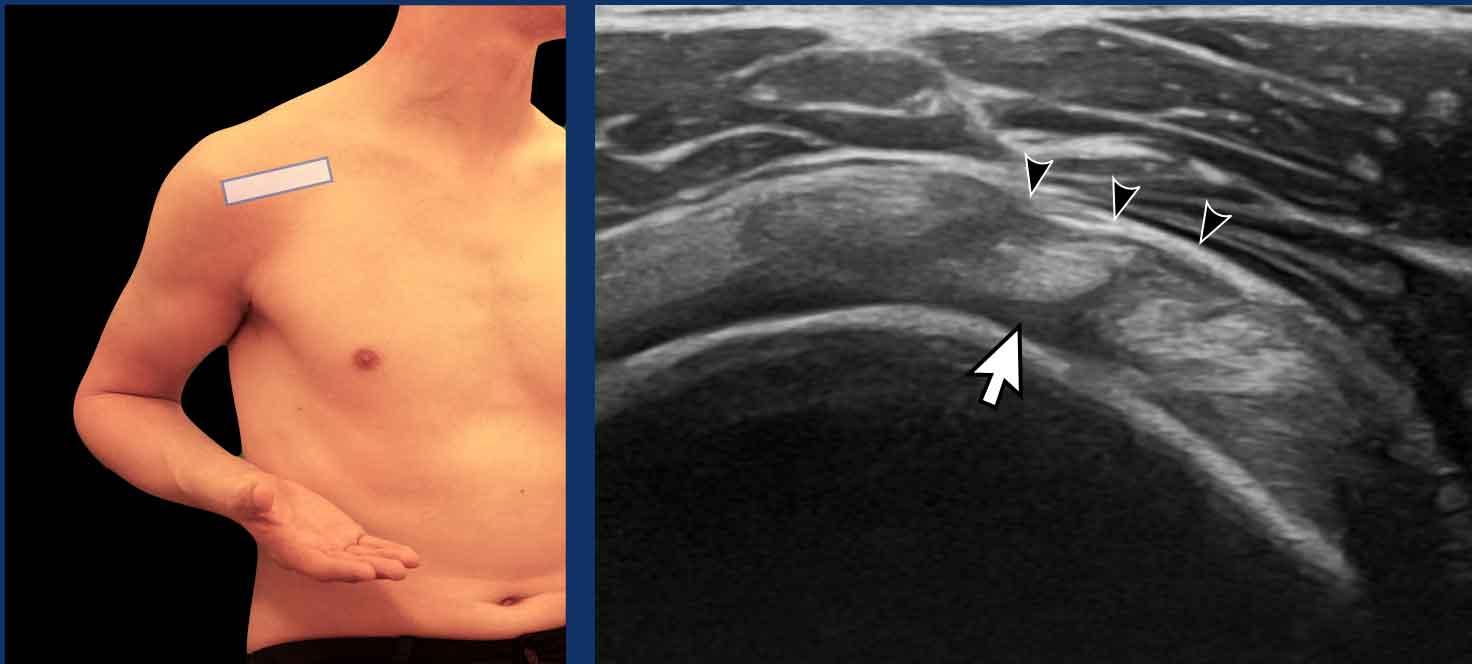

Cánh tay được đặt dọc theo thân mình, với khuỷu tay gấp góc 90º giữa cánh tay và cẳng tay.

Cẳng tay được đặt ở tư thế ngửa và xoay ngoài.

Đầu dò siêu âm được đặt ở phía trong để quan sát gân cơ dưới vai (SSC) khi nó đi qua bên dưới mỏm quạ.

Trong quá trình xoay trong và xoay ngoài của cẳng tay, toàn bộ gân phải được quan sát thấy trượt dưới mỏm quạ (xem video).

Hiện tượng chèn ép được ghi nhận khi gân di chuyển không hoàn toàn hoặc bị chậm trễ (xem chương về chèn ép).